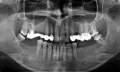

Началась боль на следующий день после установки протеза, перед установкой было проведено лечение всех зубов, нервы удалены. Стоматолог говорит о какой-то гиперчувствительности и никакого решения не предложил.

Подскажите, пожалуйста, что делать, если возникает постоянная ноющая боль под металлокерамическими мостами?

Ваш стоматолог не прав, он или лукавит, или не имеет должной квалификации, о какой гиперчувствительности идет речь? Бред! Боль после нагрузки зуба коронкой означает некачественное лечение и неправильную постановку диагноза, то есть зубы пролечены неверно, на верхушках имеются воспаления. Вам придется извлечь коронки, правильно и грамотно пролечить зубы, и только после можно протезировать. Уважаемая Евгения, пока все горячо и не прошли гарантийные сроки, рекомендую расторгнуть договор с клиникой и найти альтернативного доктора.